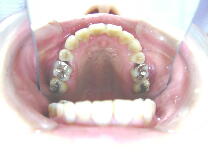

症例3 (30代 女性) 右下顎切歯先天性欠如

左右上顎第一小臼歯・右下顎第一小臼歯抜歯例

初診時